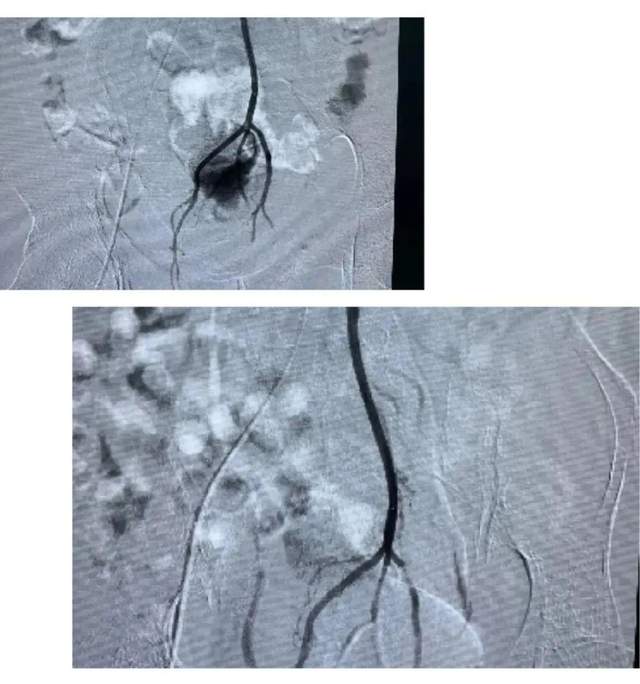

原发性肝癌血管介入

直肠癌出血栓塞

乳腺癌破溃出血

血管畸形、脾动脉破裂、肠道出血等栓塞